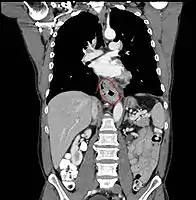

Anatomy

• Length is about 25 cm. Esophageal lesion distance on EGD is typically given from incisors

• AJCC divisions of the esophagus: (These are based on adjacent surgical landmarks)

• Cervical esophagus:

• Hypopharynx to the thoracic inlet, which is at the level of the sternal notch.

• By endoscopy, 15 to <20 cm from the incisors

• If thickening of the esophageal wall begins above the sternal notch, the location is cervical

• Upper thoracic esophagus:

• Thoracic inlet to lower border of the azygos vein

• By endoscopy, 20 to <25 cm

• Middle thoracic esophagus:

• Lower border of the azygos vein to the inferior pulmonary veins

• By endoscopy, 25 to <30 cm

• Lower thoracic esophagus and EG junction:

• Inferior pulmonary veins to the stomach; includes the intraabdominal portion of the esophagus

• By endoscopy, 30 to 40 cm